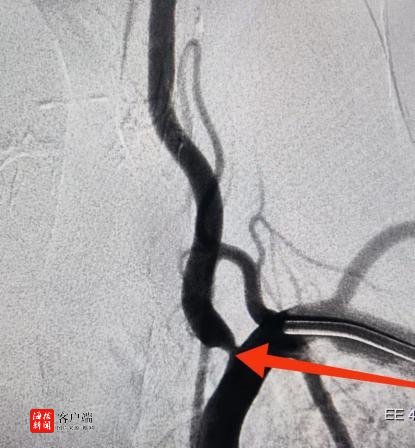

患者为一名54岁的男性,因反复头晕已持续2月有余。经过详细的术前检查,诊断为左侧椎动脉开口重度狭窄。考虑到患者的具体情况,团队决定采用新型的椎动脉药物涂层支架,并尝试从左手完成手术。这一创新方案在海南省尚属首次,目前国内仅有少数医院能够开展此类手术。

1月10日上午,在导管室技师和护士的精心配合下,介入团队顺利完成了手术。术后患者恢复良好,未出现严重并发症。目前患者病情稳定并已出院,对医护人员的专业与细心给予了高度评价。